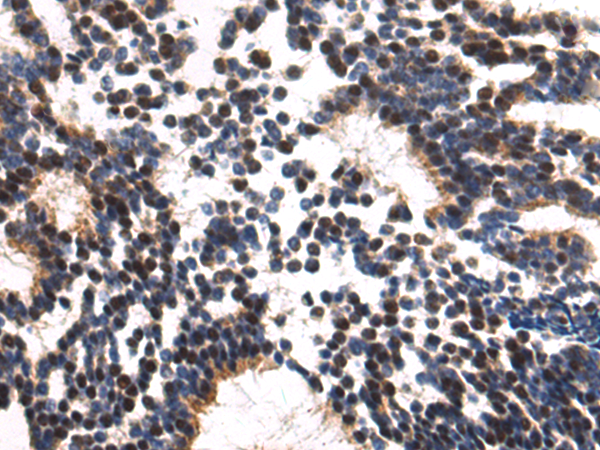

分类: 科研抗体货号: P04223别名: TOP2; TP2A应用: IHC反应种属: Human, Mouse, Rat